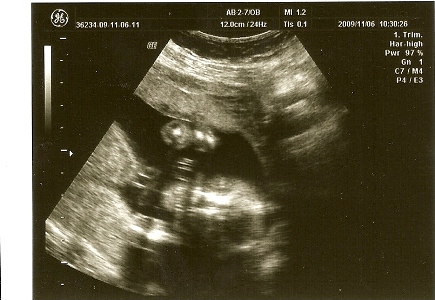

Itt egy pocakfotós kép.